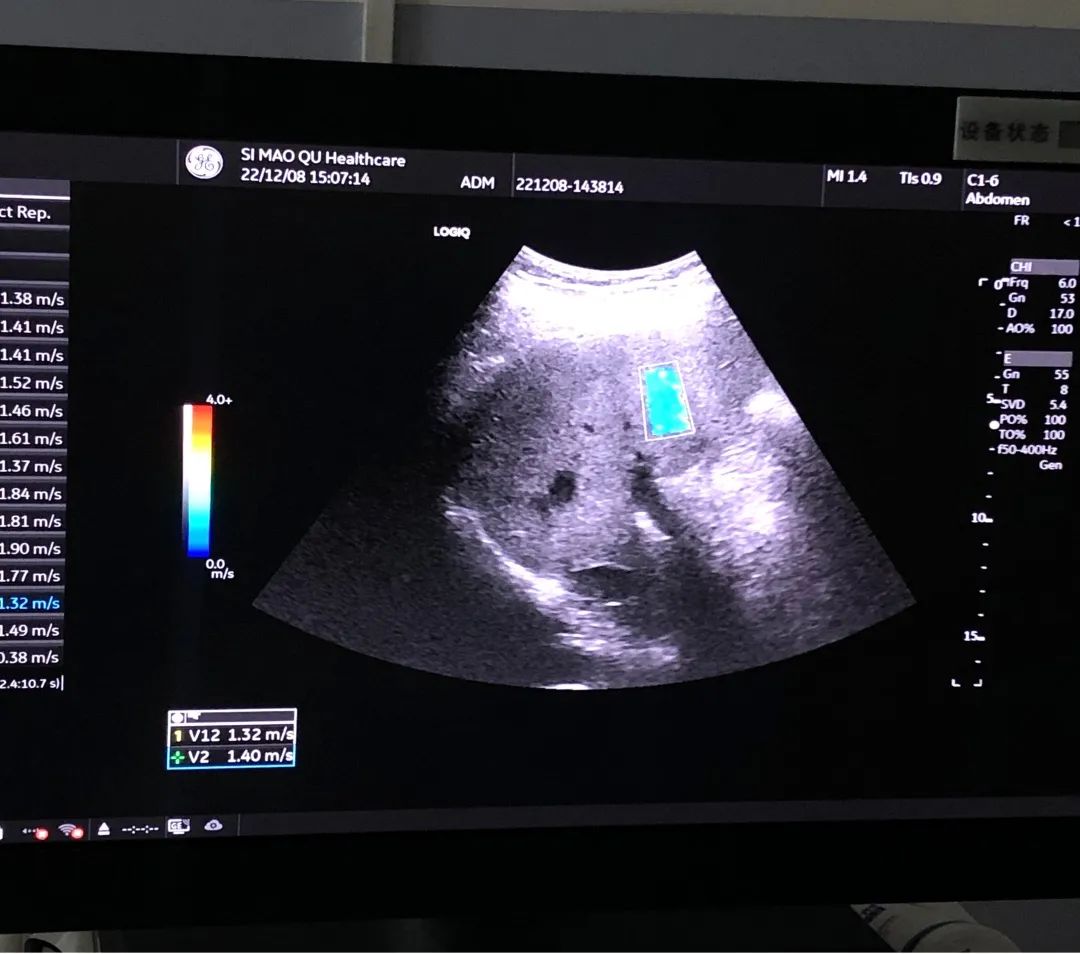

剪切波弹性成像是一种量化组织的成像模式,通过测量组织中剪切波的速度来获得组织硬度。剪切波弹性成像可以提供肝脏硬度的定量测量,用作评估纤维化的级别,这是一种非创伤性定量成像技术,可用于诊断,分期与组织弹性变化相关的疾病的管理。

普洱市中心医院(思茅区人民医院)超声医学科目前使用的GE与美国梅奥医学中心合作研发的复合剪切波弹性成像(2D-SWE),具有能量场更稳定、信息量更多、定量测量更准确、重复性更好等特点,可广泛用于腹部、浅表器官的无创定量检测,开启精准定量诊断时代。

肝脏二维剪切波弹性成像(2D-SWE)能实时定量检测肝脏硬度,评估肝脏纤维化程度,实现对慢性肝病患者病情程度的“一站式”评估。